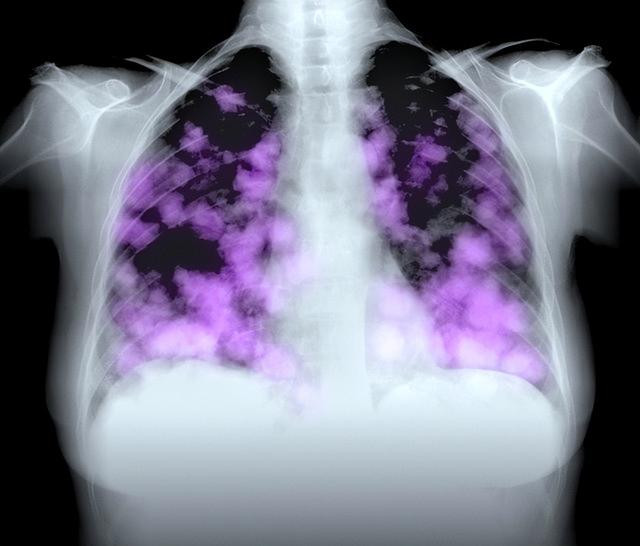

夜幕低垂,王涛(化名)静静地坐在医院的走廊里,翻看着手中的诊断报告。肺部CT上那一抹阴影,让他整个人如坠冰窟。一直以为自己身体硬朗的他,怎么也没想到——自己竟被查出了肺癌。此时,他的脑海里浮现出单位里那一群爱抽烟的同事,还有早已被自己忽视的各种生活习惯。

王涛今年45岁,从事建筑行业二十多年。因为工作压力大、应酬多,他多年来烟不离手。可让他倍感疑惑的是,身边一些“从不吸烟”的男性朋友,竟然也得了肺癌。带着疑问,王涛咨询了肿瘤科的张医生。医生的话语一针见血:“吸烟确实是肺癌的首因,但不是唯一元凶,男性肺癌高发,还和其他四个诱因密不可分。”

5.吸烟依然是头号杀手

“当然,咱们还得强调一遍。吸烟,绝对是男性肺癌主要诱因。”张医生语气郑重。“中国吸烟率仍然很高,尤其是男性。烟草里的焦油和致癌物质,对肺细胞损伤巨大。研究显示,长期吸烟者患肺癌的概率是非吸烟者的10到20倍。”

王涛深知,身边许多患肺癌的男性并非单一原因导致。吸烟、空气污染、职业暴露、遗传因素、不良生活方式,这“五重压力”一起作用,才让肺癌高发的情况愈演愈烈。